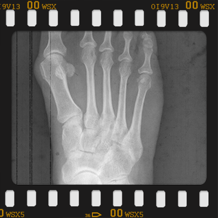

Halluk valgus ayak baş parmağının zaman içerisinde değişik nedenlerle eğilmesi ile ayak yan tarafında çıkıntının da eşlik ettiği bir rahatsızlıktır. Sıklıkla bayanlarda görülmesine rağmen erkeklerde ve çocukluk yaşlarında da karşılaşılmaktadır. Ayağın yan tarafında olan çıktı ve baş parmağın diğer parmakları itmesi ile ayakta şekil bozukluğu ve ağrı oluşur. Bu şekil bozukluğu kişinin ayakkabı giymesinde sıkıntılara neden olabilir.

Tedavisinde ayağın yük veriri pozisyonda çekilen grafileri üzerinde yapılan ölçümlerden sonra hastanın yaşı ve aktivite seviyesine göre kişiye özel planlanmaktadır. Erken dönemlerde ayakkabı modifikasyonu, parmak arası makarası ve gece ateli kullanılmaktadır. Cerrahi gerekliliğe hastanın deformitesinin büyüklüğüne ve hastanın taleplerine göre karar verilmektedir.

Aşağıdaki grafiyi öncesi sonrası şeklinde görmek için farenizi sağ sola hareket ettiriniz.

Yukarıdaki grafileri daha net ve büyük görmek için üzerine tıklayabilir. Sağ üst köşedeki + - tuşları ile daha da büyütebilirsiniz.